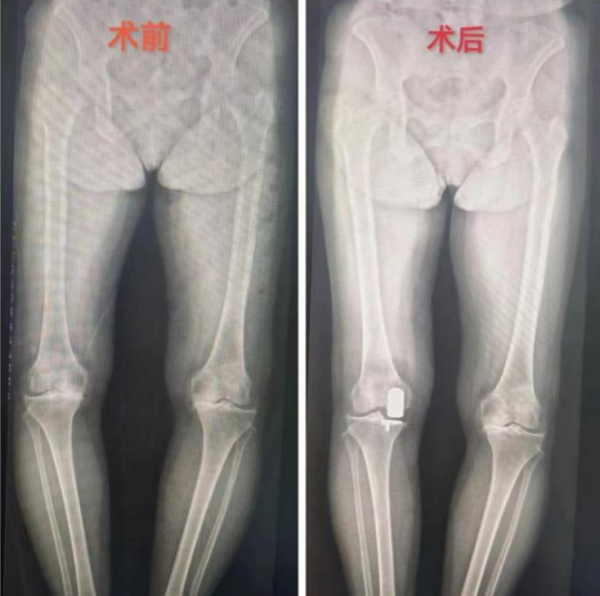

在临床案例展示部分,李良军深入讲解了来香港马会app运动医学科住院手术的老人。65岁的刘奶奶(化名),五年前确诊膝关节退行性病变,但没有接受治疗。一个月前,她的右膝关节疼痛开始异常剧烈,尤其在上下楼梯、爬坡或下蹲时加重,且活动受限明显,已经到了无法忍受的程度。在家人的陪同下,她前往运动医学科就诊。李良军阅片后,诊断刘奶奶的膝关节主要是内侧软骨磨损的特点,决定为她施行内侧单髁置换术。

李良军解释,单髁置换术相比全膝关节置换术,保留了患者没有磨损的软骨和正常的韧带,只置换了膝关节内侧或者外侧间隙磨损的那部分软骨,所以手术创伤更小、患者恢复更快,术后行动更加自如。本次手术十分成功,术后第二天,刘奶奶在病房走廊上自信地练习行走,并热情地与旁边充满好奇的病友分享自己经历,劝大家一定要早诊断早治疗。